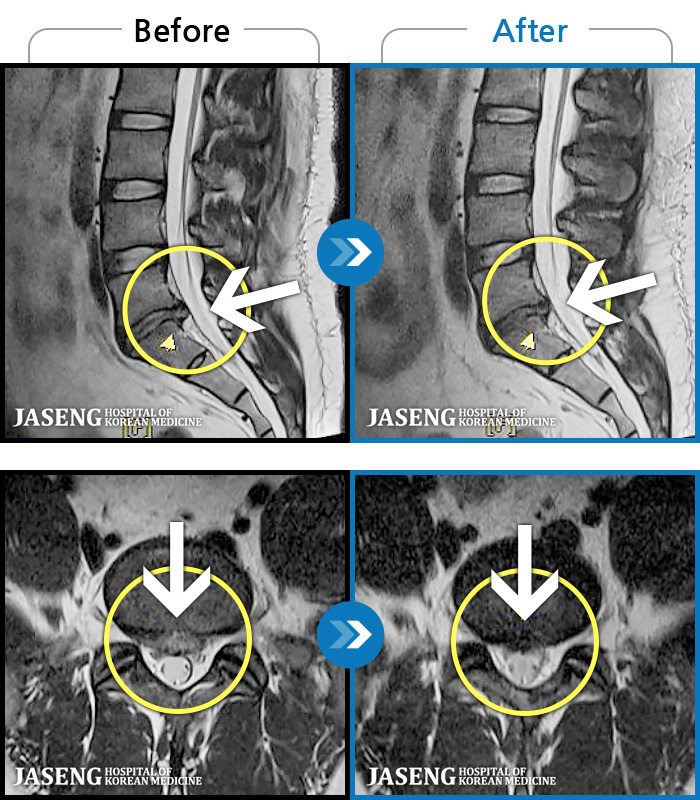

MRI ġ

1,304 MRI ũ ʸ Ȯϼ.